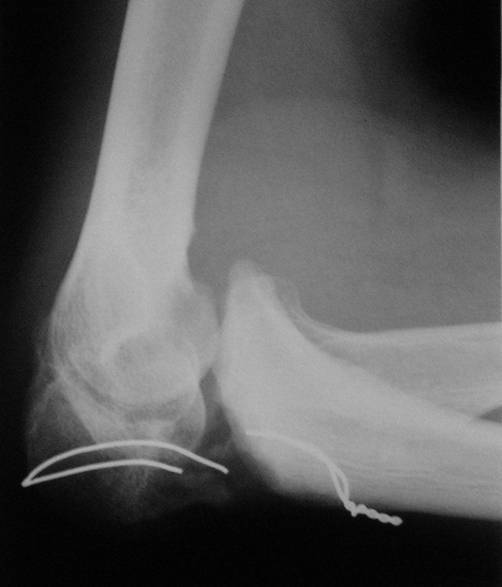

Уважаемые коллеги! Пациент 34 лет. Человек физического труда. Восемь

месяцев назад в отделение сочетанной травмы был произведен остеосинтез

локтевого отростка проволокой. В последующем занимался разработкой

сустава. Когда понял, что восстановить сустав не удастся, обратился за

помощью. Предполагает, что после операции функция сустава восстановится

полностью. Мы думаем выполнить операцию в два этапа:

1. Первый этап - аппаратом вправить предплечье 2. Второй этап -

остеосинтез локтевого отростка спонгиозным винтом, или пластиной, или по

Веберу с костной аутопластикой. Помогите советом.